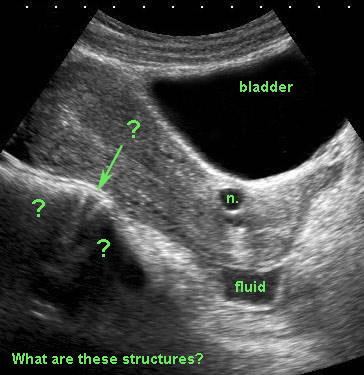

Điều quan trọng là cần hiểu rõ giải phẫu ngoài tử cung.

Một ít dịch trong túi cùng Douglas và một nang Naboth nhỏ (n.) có thể dễ dàng nhận biết, nhưng các cấu trúc được đánh dấu bằng dấu chấm hỏi là gì?

Lưu ý bàng quang căng đầy đang đẩy tử cung ra phía sau.